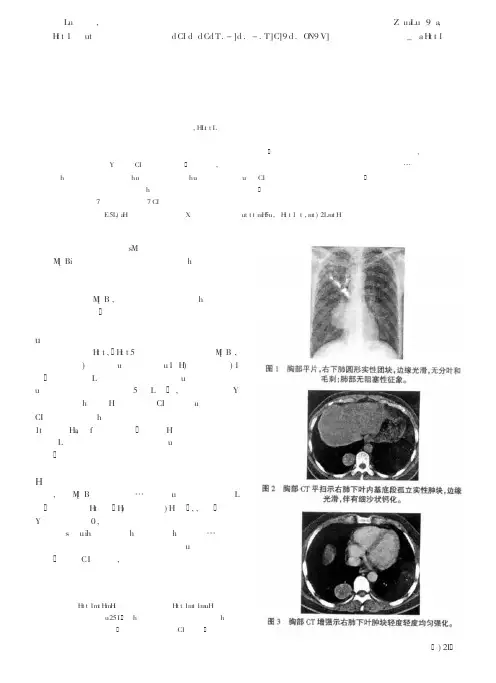

肺硬化性血管瘤的CT表现刘铁利;田明;赵海艳;葛莹;李智勇;伍建林【期刊名称】《大连医科大学学报》【年(卷),期】2007(29)4【摘要】[目的]探讨肺硬化性血管瘤的CT表现特征,以提高其CT诊断准确性.[方法]回顾性分析5例经手术和病理证实的肺硬化性血管瘤的CT表现,其中1例行CT 增强扫描.[结果]5例肺内类圆形肿块边界清楚,2例见斑点状钙化,2例见浅分叶,1例有纵隔淋巴结肿大,所有病例均无毛刺和空洞,无胸膜凹陷和受侵,无血管切迹征.CT 值为26~35 Hu.[结论]CT对于肺硬化性血管瘤具有一定的诊断价值.【总页数】2页(P371-372)【作者】刘铁利;田明;赵海艳;葛莹;李智勇;伍建林【作者单位】大连医科大学,医学影像学系,辽宁,大连,116027;大连医科大学,第一临床学院,放射科,辽宁,大连,116011;大连医科大学,第一临床学院,放射科,辽宁,大连,116011;大连医科大学,第一临床学院,放射科,辽宁,大连,116011;大连医科大学,第一临床学院,放射科,辽宁,大连,116011;大连医科大学,第一临床学院,放射科,辽宁,大连,116011【正文语种】中文【中图分类】R445【相关文献】1.肺硬化性血管瘤的CT表现 [J], 陈玲;侯书法;翟建;吴琛;张超;童梦玲;周峰峰2.研究肺硬化性血管瘤CT表现与病理基础 [J], 钟灵心3.研究肺硬化性血管瘤CT表现与病理基础 [J], 钟灵心;4.肺硬化性血管瘤MSCT表现特征及病理学基础 [J], 殷灿; 虞浩; 陆菲菲; 陈自谦5.肺硬化性血管瘤多层螺旋CT影像表现特点探讨(附18例分析) [J], 杨素梅;马存文;沈开明;胡瑞;蔡雁凌因版权原因,仅展示原文概要,查看原文内容请购买。

结果:11例PSH中,男性2例及女性9例,均为单发结节病灶,发生于右肺6例,左肺5例,大小6mm×8mm~33mm×47mm,CT平扫均表现为边界清楚、密度均匀的圆形或卵圆形软组织密度影,3例见浅分叶征,2例可见胸膜凹陷征,2例病灶边缘部分见沙粒状钙化,均未见毛刺征,增强扫描呈持续性进行性显著强化,动脉期、实质期CT值比平扫平均增加31HU 和62HU,4例PSH动脉期见贴边血管征。